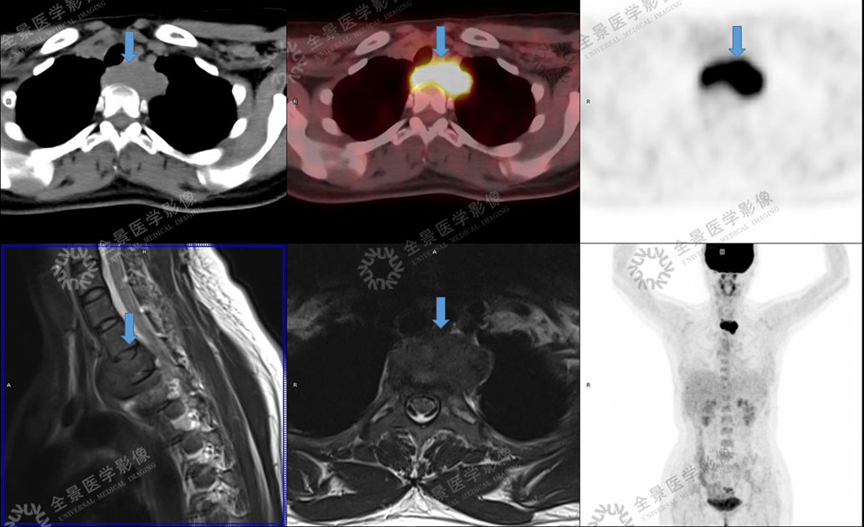

骨关节

案例 :骨巨细胞瘤

T2WI不均匀等信号,

PET/CT显示:T3骨质破坏并周围软组织肿块形成,FDG明显摄取增高。

增强扫描明显强化